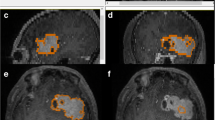

Seventeen studies addressed the first question and the results of quality assessment are summarized in Fig. 2 and Table 2 [9, 20,21,22,23,24,25,26,27,28,29,30,31,32,33,34,35]. For risk of bias, the quality was variable across each domain. In the patient selection domain, 10 were judged to be at low risk [9, 20,21,22, 26, 30,31,32,33,34,35] and 7 were considered high risk [23,24,25, 27,28,29]. In the index test domain, 9 studies were considered low risk whilst the remaining 8 were unclear in risk. For the reference standard domain, all studies were deemed low risk. Regarding flow and timing, 11 studies had low risk, 2 studies had high risk and 4 studies had unclear risk. For applicability, all studies across all domains were considered low risk.

For the second question, looking at the role of DKI in differentiating glioma from non-gliomatous CNS tumours, our literature search only identified two studies which did not allow us to obtain any conclusive results [18, 19]. These studies showed however encouraging results that need to be reproduced in the future. Yan Tan et al. analysed MK values in solid tumour parts and the periphery of high-grade astrocytomas (HGAs) and solitary metastatic lesions, concluding that MK values differed significantly in the periphery between the two entities. MK values were also more sensitive than diffusion tensor imaging (DTI) metrics [19]. Using DKI, Pang et al. aimed to differentiate between HGGs and primary CNS lymphomas (PCNSLs) [18]. They reported significantly higher MK in PCNSLs than HGG, which could perhaps be explained by the hypercellular nature of lymphomas microenvironment.